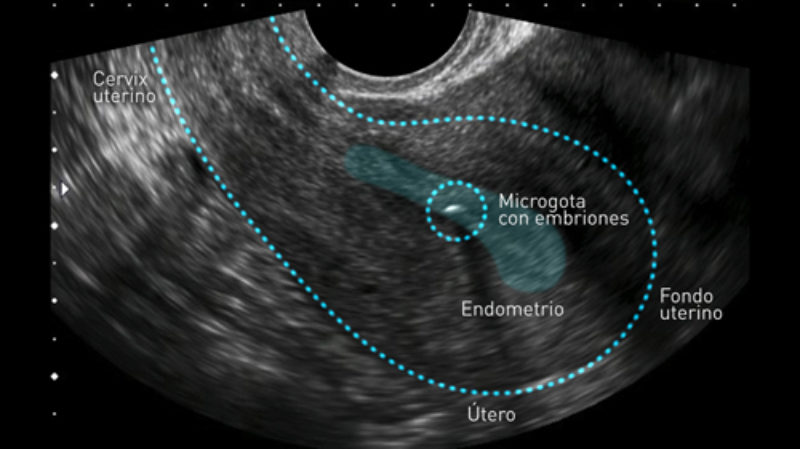

El útero mueve los embriones para que se implanten correctamente

Nuevas imágenes permiten ver cómo el endometrio se mueve para mantener el embrión dentro de la cavidad uterina e impedir su expulsión o implantación en un lugar inadecuado. El hallazgo revela que no es necesario guardar reposo y permite cambiar la pauta médica que se da las pacientes después de la transferencia de embriones.